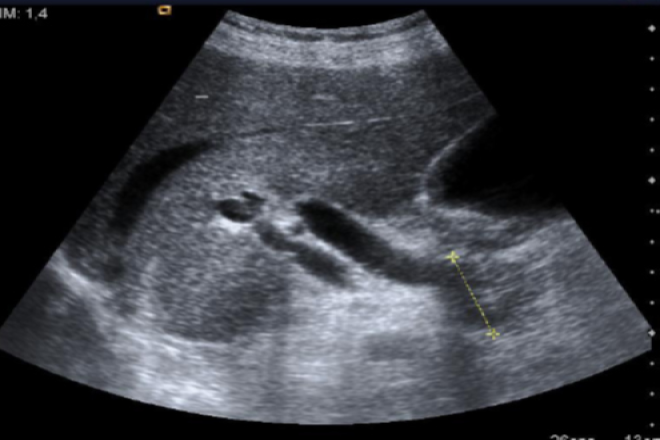

Conducto de Wirsung: Con una longitud de 9.5 cm y un diámetro de 2 mm, se origina en la cola y sigue el eje mayor del cuerpo del páncreas. En la cabeza, se sitúa posteriormente y se inclina hacia la derecha describiendo una forma de S. Se une al colédoco cerca de la pared duodenal y desemboca en la ampolla de Vater, abriéndose en el duodeno en su cara posterior interna, cerca de la segunda porción del mismo.